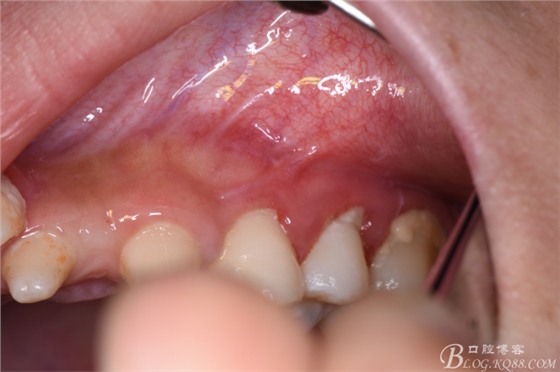

圖5.口內(nèi)觀:22、23區(qū)域的牙齒均為過(guò)小牙、牙冠畸形,24根尖區(qū)未能捫及明顯隆起,但cbct的精準(zhǔn)定位,確定切口應(yīng)做在24根尖區(qū)的前庭溝內(nèi)。

圖6.患者的口腔衛(wèi)生不佳,建議潔牙。